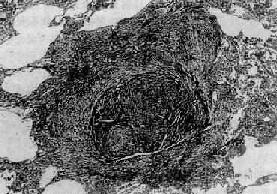

图9-22 矽肺 矽结节,由呈旋涡状排列的已发生玻璃样变的胶原纤维构成

(一)矽肺 矽肺(silicosis)是在生产环境中长期吸入大量含游离二氧化硅(SiO2)粉尘微粒所引起的以肺纤维化为主要病变的全身性疾病。游离二氧化硅主要存在于石英中,石英成分中SiO2占97%~99%。约有70%的矿石中均含有较多的SiO2。长期从事开矿、采石作业、坑道作业以及在石英粉厂、玻璃厂、耐火材料厂、陶瓷厂和搪瓷厂生产作业的工人易患本病。矽肺是危害最严重的一种职业病,其特点是发展缓慢,即使在脱离矽尘作业后,病变仍然继续缓慢发展。患者多在接触矽尘10~15年后才发病。若因吸入高浓度、高游离二氧化硅含量的矽尘,经1~2年后发病者,称速发型矽肺。矽肺的早期即有肺功能损害,但因肺的代偿能力很强,患者往往无症状,随着病变的发展,尤其是合并肺结核和肺心病时,则逐渐出现不同程度的呼吸和心功能障碍。 病因和发病机制 游离二氧化硅是矽肺的致病因子。矽肺的发生、发展与矽尘中游离二氧化硅的含量,生产环境中矽尘的浓度、分散度,从事矽尘作业的工龄及机体防御功能等因素有关。矽尘粒子愈小,分散度愈度,在空气中的沉降速度愈慢,被吸入的机会就愈多,致病作用亦愈强。一般来说,大于5μm的矽尘往往被阻留在上呼吸道,并可被呼吸道的防御装置清除。小于5μm的矽尘才能被吸入肺泡,并进入肺泡间隔,引起病变。尤以1~2μm的矽尘微粒引起的病变最为严重。 吸入肺泡内的矽尘微粒被肺巨噬细胞吞噬,沿肺淋巴流经细支气管周围、小血管周围、小叶间隔和胸膜再到达肺门淋巴结。当淋巴道阻塞后,矽尘沉积于肺间质内引起矽肺病变。若局部沉积的矽尘量多,引起肺巨噬细胞局灶性聚积,可导致矽结节形成;若矽尘散在分布,则引起弥漫性肺间质纤维化。矽肺的发病机制尚未完全阐明。一般认为,矽尘被肺巨噬细胞吞噬后,在游离二氧化硅的毒性作用下,巨噬细胞大量死亡崩解或发生功能和生物学行为改变,释放出一些致纤维化因子、包括巨噬细胞生长因子(MDGF),白细胞介素Ⅰ(IL-1)和纤维连结蛋白(FN)等,促进成纤维细胞增生和胶原形成,导致纤维化。至于巨噬细胞死亡的原因,主要是由于矽尘被巨噬细胞吞噬后,存在于次级溶酶体中,矽尘表层中的SiO2逐渐与水聚合成硅酸(系一种强的成氢键化合物),其羟基基团与溶酶体膜脂蛋白结构上的受氢原子(氧、氮或硫)间形成氢键,改变了溶酶体膜的脂质分子构型,从而破坏了膜的稳定性或完整性。溶酶体膜通透性增高或破裂,其中所含的大量水解酶溢出到细胞内,导致巨噬细胞自溶崩解。巨噬细胞死亡崩解后,释出的矽尘又被其它巨噬细胞吞噬,如此反复进行,使病变不断发展、加重。这也可解释何以患者脱离矽尘作业后肺部病变仍然会继续发展的缘由。 随着免疫学的发展,大量关于矽肺免疫的研究表明,在矽肺发生、发展过程中,有免疫因素参与。根据对矽结节玻璃样变组织的生化分析,其中球蛋白含量明显高于胶原含量,而有别于一般的玻璃样变组织的成分。动物实验证明,矽肺病变的纤维化程度与浆细胞反应强度呈正相关,提示矽肺的纤维化与抗原抗体反应有关。用荧光免疫组织化学方法观察矽结节,发现在胶原纤维及其间隙中有大量γ-球蛋白沉积,主要是IgG和IgM。如将尸检取得的矽结节玻璃样变组织制成匀浆,给家兔注射后,能产生抗人γ-球蛋白抗体。有人认为,浆细胞产生的免疫球蛋白通过形成抗原抗体复合物参与矽肺的发病。对矽肺患者作体液免疫测定发现,血清中IgG和IgM浓度增高,抗肺自身抗体、抗核抗体和类风湿因子检出率也较高。但关于矽肺免疫的抗原物质目前还未提取出来,多认为有3种可能性:①矽尘作为半抗原与机体的蛋白质结合构成复合抗原;②矽尘表面吸附的γ-球蛋白转化为自身抗原;③矽尘导致巨噬细胞死亡崩解后释放自身抗原。现已有很多证据表明,巨噬细胞死亡崩解后释放抗原的可能性最大。总之,矽肺的病因是明确的,发病机制极为复杂,在发病过程中可能有多种因素参与,它们互相影响、互为因果,共同促进矽肺的发生和发展。 病理变化 矽肺的基本病变是肺组织内矽结节形成和弥漫性间质纤维化。矽结节是矽肺的特征性病变,结节境界清楚,直径2~5mm,呈圆形或椭圆形,灰白色,质硬,触之有砂样感。随着病变的发展,结节可融合成团块状,在团块的中央,由于缺血、缺氧而发生坏死、液化,形成矽肺性空洞(silicotic cavity)。矽结节的形成过程大致分为三个阶段:①细胞性结节,由吞噬矽尘的巨噬结胞局灶性聚积而成,巨噬细胞间有网状纤维,这是早期的矽结节;②纤维性结节,由纤维母细胞、纤维细胞和胶原纤维构成;③玻璃样结节,玻璃样变从结节中央开始,逐渐向周围发展,往往在发生玻璃样变的结节周围又有新的纤维组织包绕。镜下,典型的矽结节是由呈同心圆状或旋涡状排列的、已发生玻璃样变的胶原纤维构成(图9-22)。结节中央往往可见内膜增厚的血管。用偏光显微镜观察,可以发现沉积在矽结节和肺组织内呈双屈光性的矽尘微粒。除矽结节外,肺内还有不同程度的弥漫性间质纤维化(图9-23),范围可达全肺2/3以上。此外,胸膜也因纤维组织弥漫增生而广泛增厚,在胸壁上也可形成胸膜胼胝,甚至可厚达1~2cm。肺门淋巴结内也有矽结节形成和弥漫性纤维化及钙化,淋巴结因而肿大、变硬。